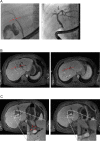

Case presentation: A 65-year-old Caucasian male presented with painless jaundice caused by an undifferentiated carcinoma in Klatskin-position (Type IIIb). Alpha fetoprotein (AFP; 3675 IU/mL) and carbohydrate antigen 19-9 (CA 19-9; 183 U/ml) were elevated. An exploratory laparotomy was carried out, but the patient was found to be irresectable due to severe fibrosis caused by biliary obstruction. Histology showed an undifferentiated carcinoma with high proliferation rate, and the patient was therefore subjected to poly-chemotherapy treatment according to the FOLFOX6-protocol. During therapy, AFP decreased to normal. Subsequent CT scans and ERC revealed a complete remission. Four years past initial diagnosis, a new suspicious lesion in the liver is visible on MRT; however, AFP and CA 19-9 are still in the normal range.